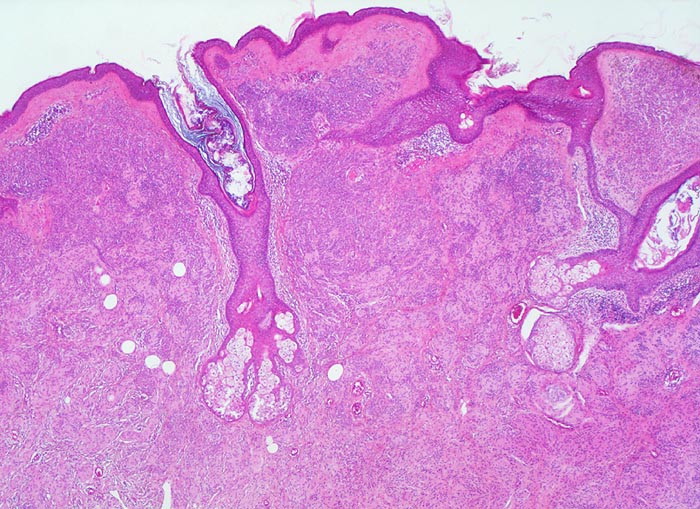

PathoPic – image database / PathoPic ID 3575 - dermaler Naevuszellnaevus

dermaler Naevuszellnaevus

Unauffällige Epidermis mit Haarfollikeln. Grosse konfluierende Nester von Naevuszellen füllen das Corium aus. Zwischen den Naevuszellen und der Epidermis schmale Schicht von zellarmem Bindegewebe (corialer=dermaler Naevuszellnaevus).

Graubraune, leicht erhabene, scharf begrenzte Hautveränderung über dem Schulterblatt.

Histologie

25